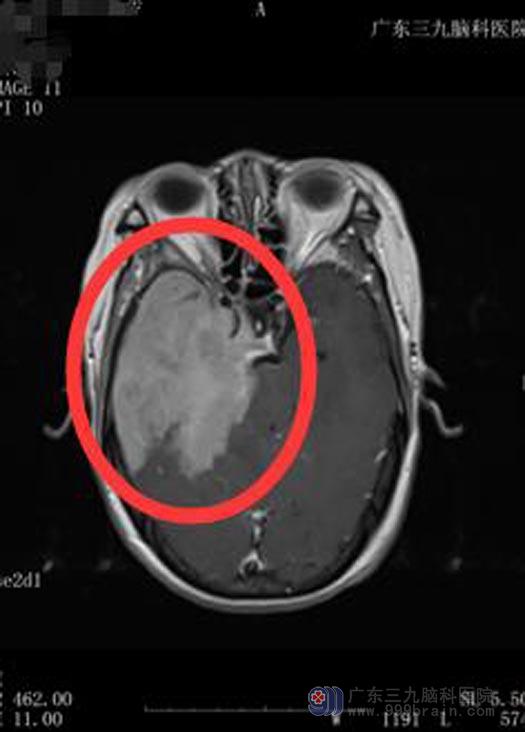

正在他们非常庆幸当初选择的时候,王阿姨突然没有任何诱因地出现头痛头晕、面部麻木、右眼闭合不全、耳朵听不见、意识不正常等症状。王阿姨一家赶紧来到广东三九脑科医院综合神经外科,经检查发现:肿瘤组织巨大,周围组织水肿明显,相应颅底骨质破坏严重,